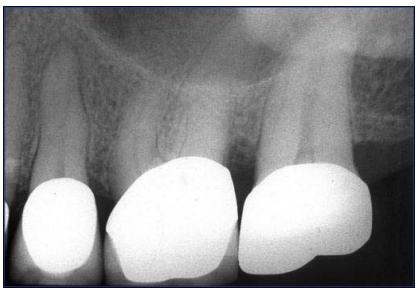

18. 李伯伯兩週前上顎左側開始對冷水刺激感到不適,症狀逐漸嚴重故求診,其X光片結果如下圖所 示,對於此症狀的診斷,下列何者正確?

(A)第二小臼齒因牙冠內再度齲齒(recurrent decay),需進行根管治療 (B)第一大臼齒因根管系統鈣化,需進行根管治療 (C)第二大臼齒因根管內吸收,需進行根管治療 (D)無法由此X光片判斷何者需根管治療